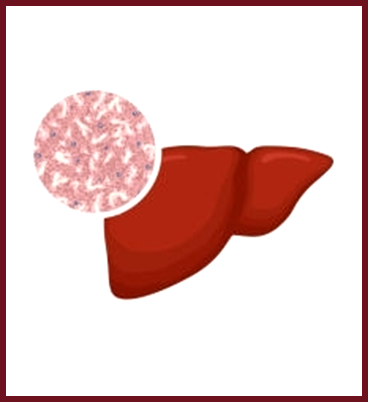

PBC a chronic disease characterized by progressive inflammation and destruction of small bile ducts within the liver. The bile ducts transport bile from the liver to the intestine for the absorption of fat and elimination of waste products.